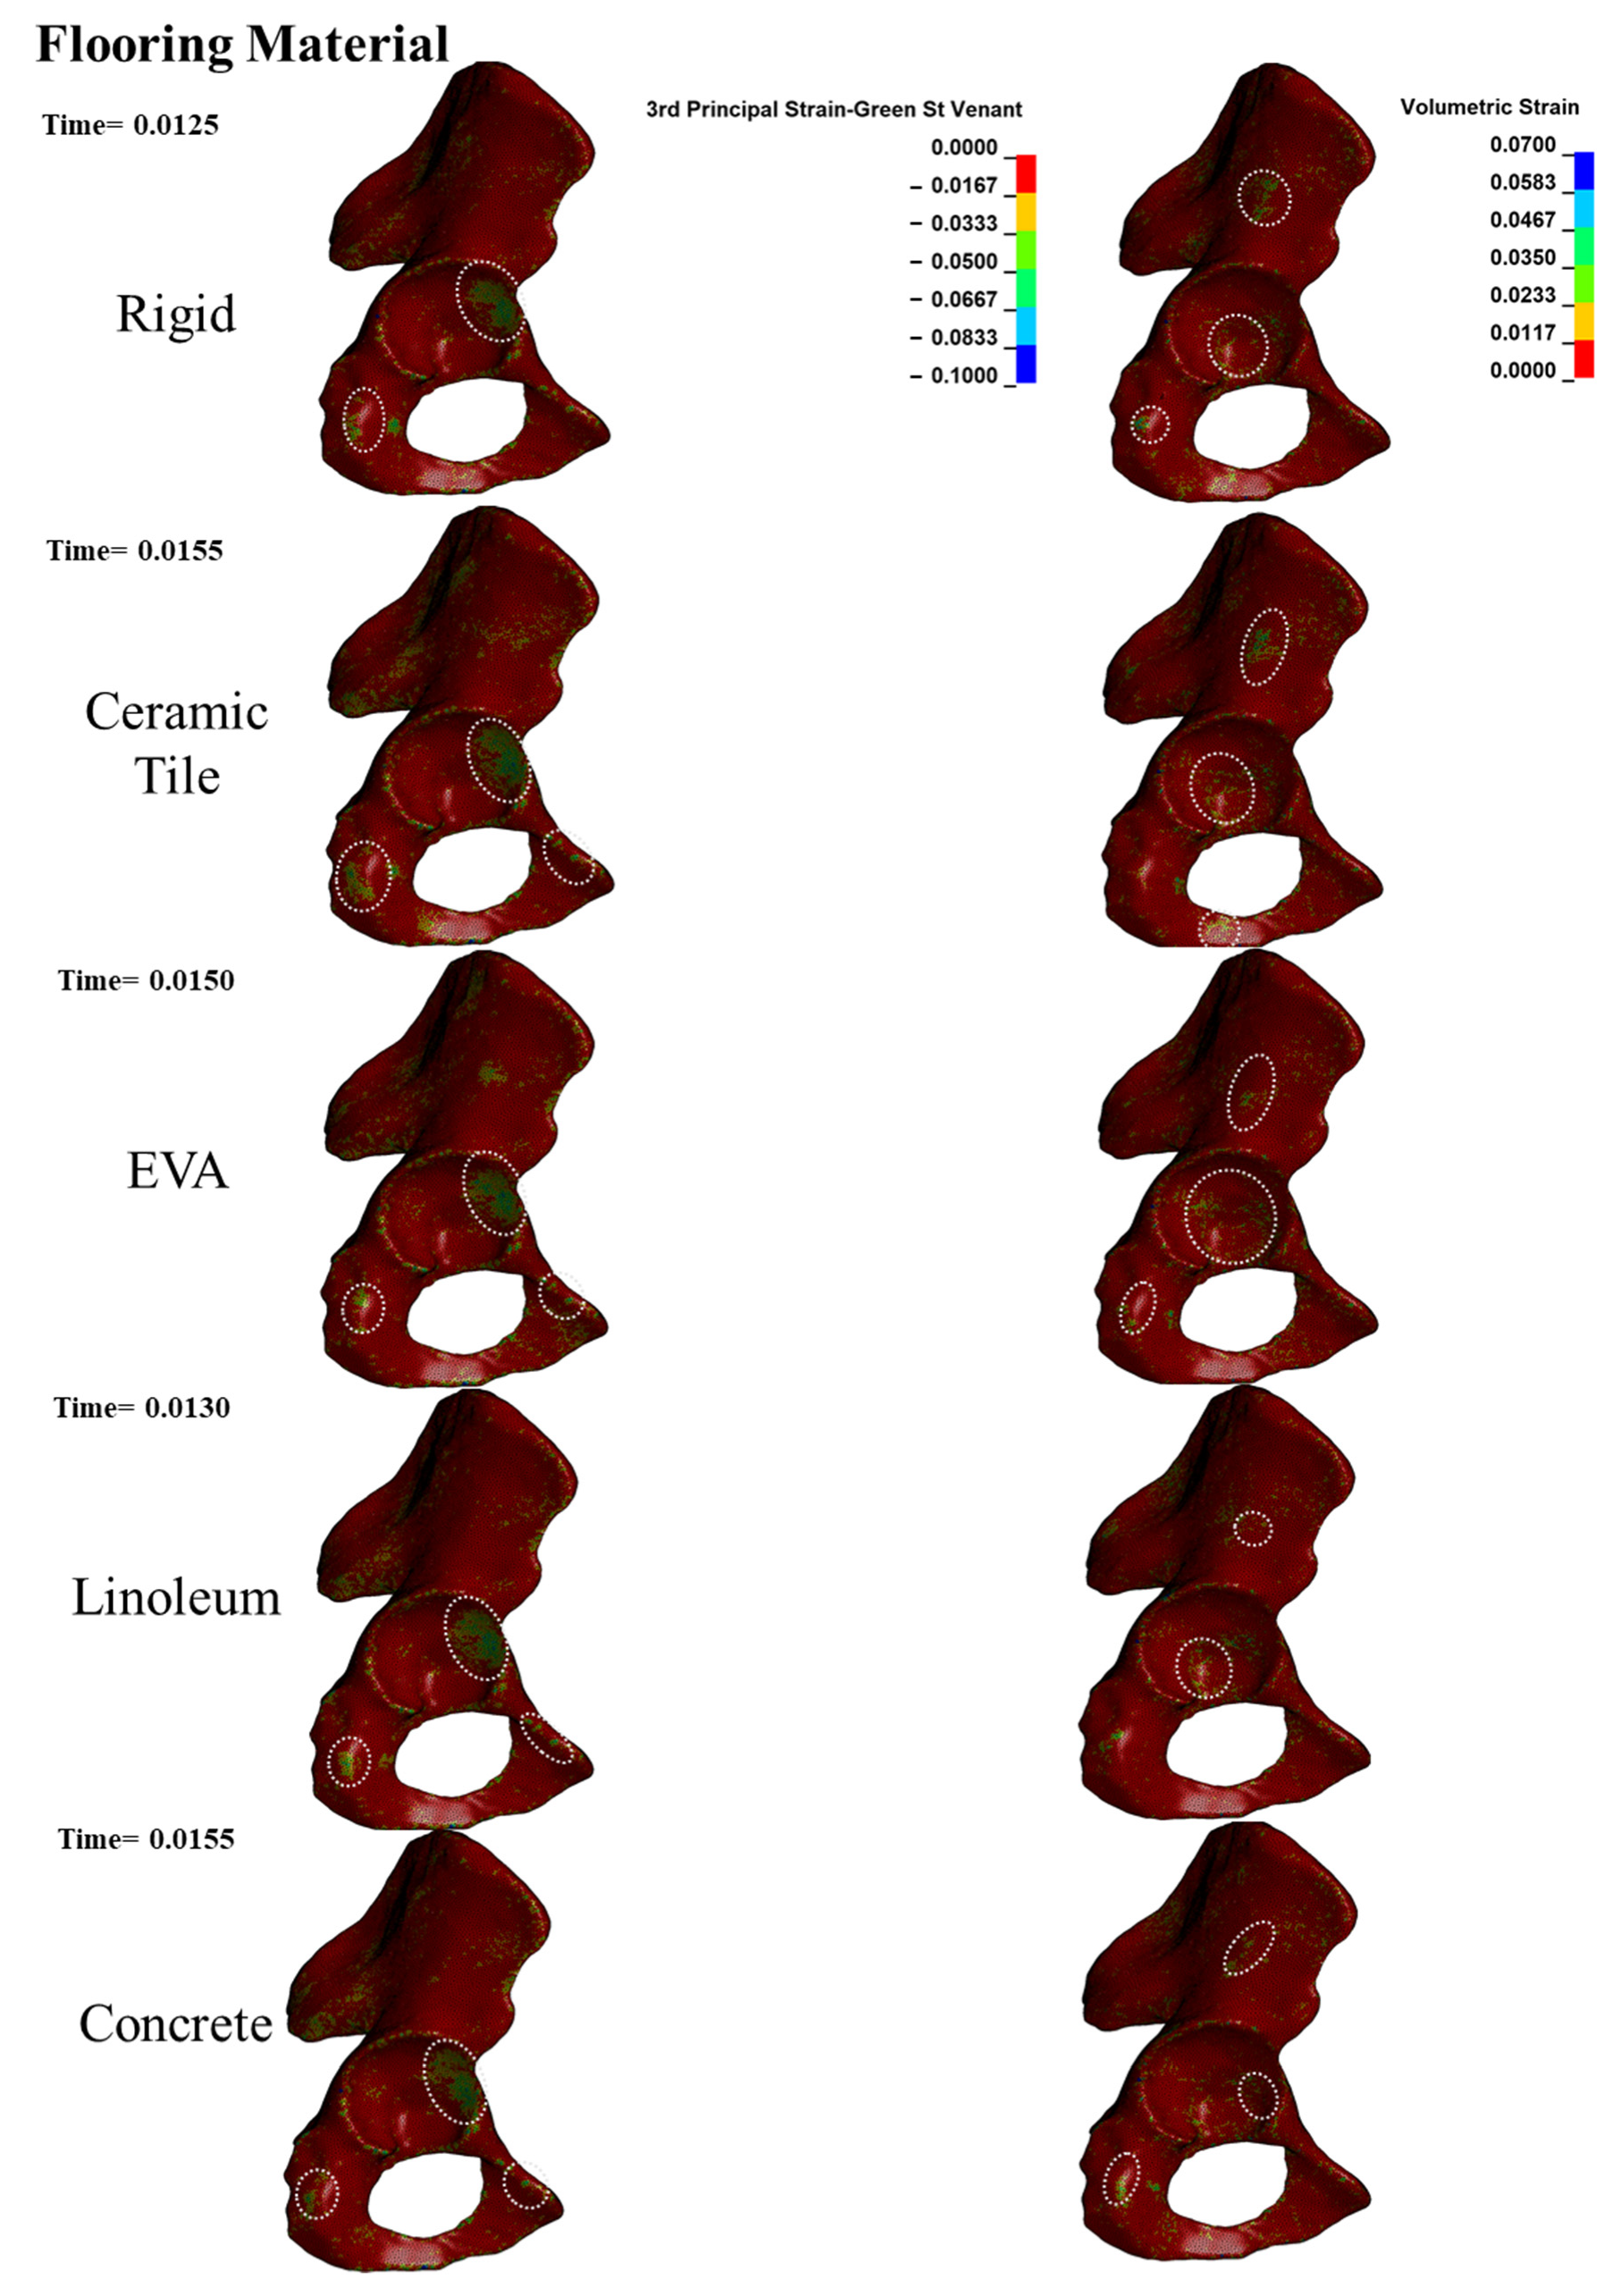

3.3. Bone Failure Type

| Conventional flooring material | Rigid *, ceramic tile, ethylene-vinyl acetate, linoleum, concrete, plywood, asphalt pavement, agglomerated cork |